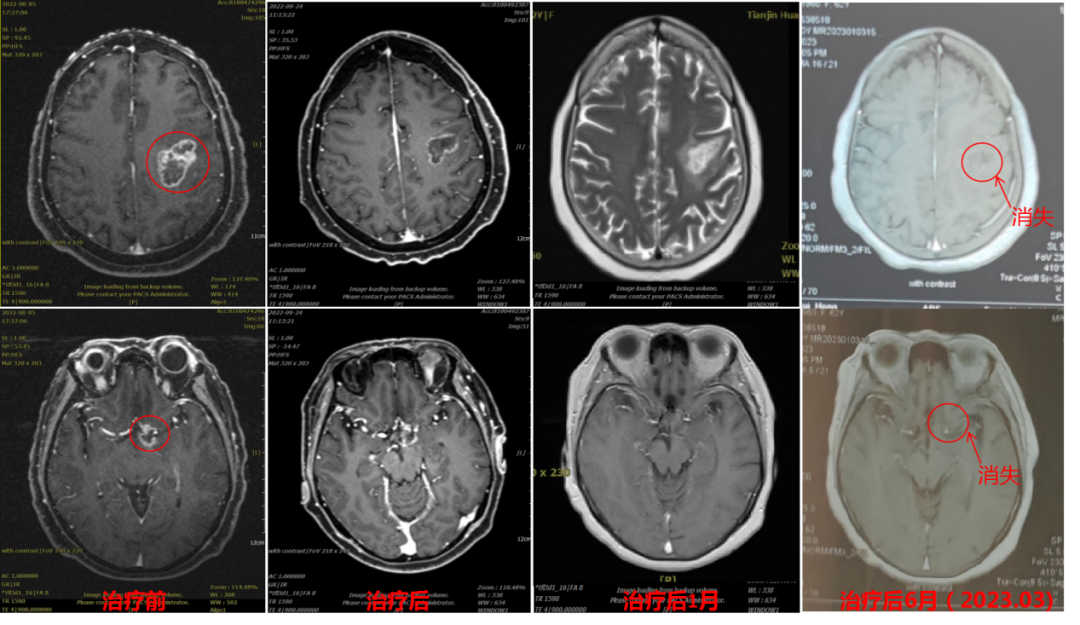

病例二

85岁高龄,入院前出现左侧肢体麻木、无力,肢体活动障碍,反应迟缓、小便失禁。头颅核磁提示右侧额叶-胼胝体区胶质母细胞瘤。

图3 碳离子治疗期间的影像对比

图4

病例三

33岁,回族,入院3月前行脑胶质瘤手术,病灶大部分切除,但仍有残留,术后肢体无力未缓解,诊断为:(右侧额顶叶)胶质母细胞瘤 WHO IV级,治疗前左侧肢体肌力3级,治疗后左侧肢体肌力基本恢复。

图5 光子联合碳离子治疗剂量图

图6

病例四

中年女性,入院前出现渐进性言语不畅,MET-PET示:左侧额叶、左侧脑室旁、鞍上池多发MET及FDG异常高代谢灶,深圳当地医院取检后诊断为胶质母细胞瘤 WHO IV级,入院时言语不畅,定向力减退。治疗后言语不畅及定向力恢复(见图7)。

图7